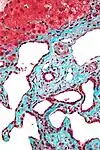

| Tinción tricrómica de Masson | Tricrómica |

|

Se tiñen fibras, tejido muscular y citoplasmas, donde destaca esencialmente el condrioma como un fino granulado rojizo. Sin embargo, por su pH ácido, que se encuentra entre 2.5 y 2.7 (ligeramente por encima del óptimo para la tinción del colágeno), se presenta como una tinción incompleta y difusa del componente fibrilar más fino (membrana basal y finas fibras reticulares). | ![]() |